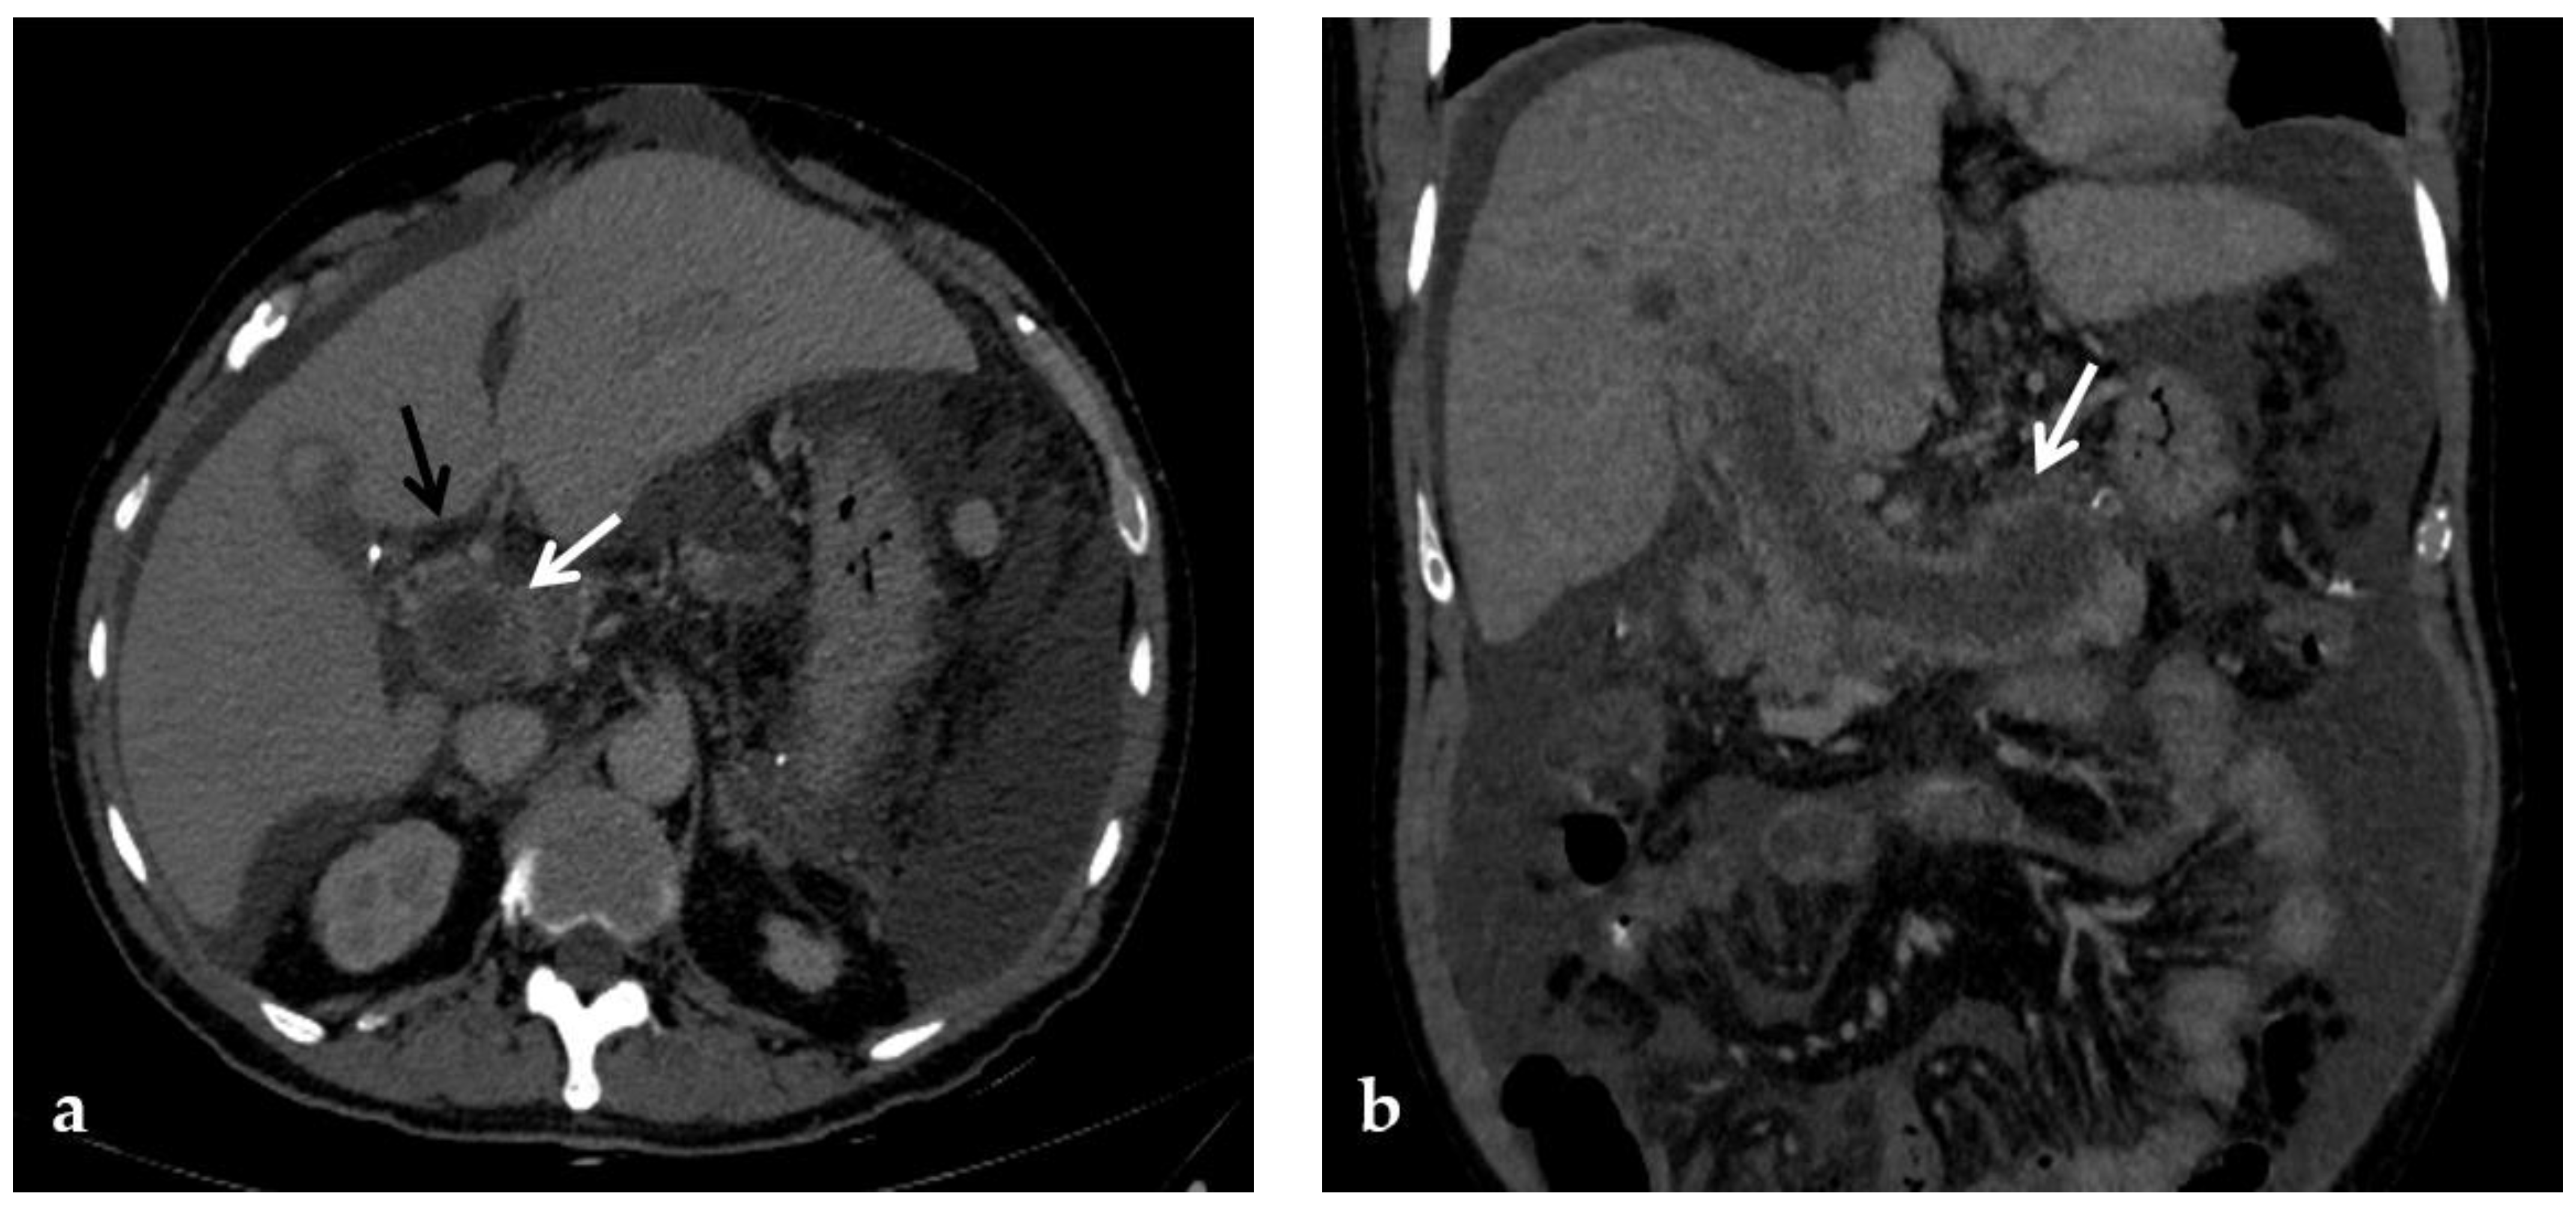

Figure 4.

CT images of portal vein thrombosis in a 62-year-old male affected by myelofibrosis, who presented with intense abdominal pain. (a) Portal phase axial CT image shows a lack of luminal enhancement in the porta hepatis, increased portal vein caliber with enhancing walls, and a low-attenuating thrombus within the lumen, consistent with acute portal vein thrombosis (white arrow). Multiple collateral vessels forming a cavernoma are seen at the hepatic hilum (black arrow). (b) Portal phase coronal CT image better shows the extension of portal vein thrombosis, also involving the splenic vein (arrow).